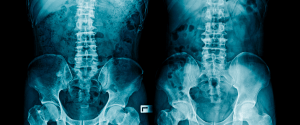

As the U.S. emerges from the COVID-19 pandemic, orthopedics should bounce back, as patients will seek out surgery to remedy discomfort or pain. The sector will rebound due to the nature of the ailments it treats, which come mostly in the form of everyday injuries that generate fractures as well as joint replacements. Whereas people might have the ability to function normally with dermatology or ophthalmology issues, when they have fractures, a spine problem, or back pain, they can’t function.

Another boon for the orthopedics field is that as the baby boomer population continues to age, they’ll need joint surgery. As imaging technology improves, doctors are recommending total replacement of shoulders, ankles, knees, and hips, as well as joint resurfacing. With tech improvements, the risk factors are lower, turnaround time is faster, and recovery periods are better. A lot of these procedures can be done on an outpatient basis, and members of the older population are accessing these services more. These procedures allow them to become active again – they can play golf, see their grandkids, and drive.

As orthopedic groups increase in size, the opportunity increases for additional business lines. Larger groups may have multiple locations and offer a different set of ancillary services. One of the big opportunities lies in advanced technology for imaging, an MRI machine. Every orthopedic practice tries to own their own MRI machine, which runs between $2 million and $3 million. A practice of 10 to 15 surgeons can produce 5,000 MRIs a year, with an average yield of about $700 each. It’s a revenue stream that doesn’t rely on physicians’ hands.